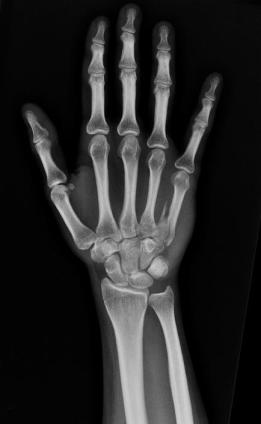

Su mano es su mano, y además

es un catálogo de caricias

y el patrón de las dimensiones

planetarias.

Es su mano, y también es

el aforo completo de la sala,

los surcos arando la tierra

y el inventario de las sombras.

Alza la mano y es, por supuesto,

su mano alzada, pero también

es una azotea con sábanas tendidas

y la vela hinchada a la deriva.

Viene su mano a la mía, y son,

amén de dos manos entrelazadas,

un hito en la historia, un reloj vacío,

un manantial silencioso, un apaño

entre el agua y el aire

en el que se miden las cosas

por el calor que emiten, por la luz

que ofrecen, por ese sistema métrico

extraño, divino y milagroso.